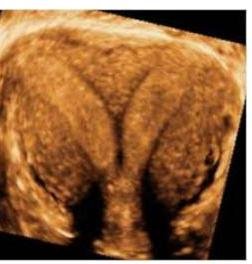

# LIIFERTILIDAD y ESTERILIDAD ## DEFINICIÓN INFERTILIDAD: FALLA de una pareja para CONCEBIR POSTERIOR A 12 MESES DE RELACIONES SEXUALES sin el uso de anticoncepción, en mujeres menores de 35 años de edad o posterior a 6 meses en mayores de 35 años. ESTERILIDAD: Es un término que ANTERIORMENTE se utilizaba para designar a los pacientes que lograban tener una prueba de embarazo positiva pero que tenían perdidas constantes del producto sin poderlo llevar a término. - Esterilidad Primaria: incapacidad de conseguir una gestación espontánea desde el inicio de las relaciones sexuales sin que, al menos durante un año, se hayan utilizado anticonceptivos. - Esterilidad Secundaria: incapacidad de conseguir una gestación espontánea tras la consecución previa de un embarazo. ## EPIDEMIOLOGÍA - Prevalencia de la infertilidad de 9 %. - La principal causa de infertilidad femenina es la ANOVULACIÓN - Principal causa de infertilidad masculina VARICOCELA - Actualmente, los embarazos por fertilización in vitro representan el 1-3 % de los nacidos vivos en países desarrollados. - El 5 % de las parejas tiene infertilidad inexplicable y 15 % logrará un embarazo durante su estudio. ## FACTORES DE RIESGO - Mujer >35 años - Oligomenorrea - Endometriosis - Cirugía pélvica previa - Síndrome de Ovario Poliquísticos - Leiomiomas (Miomatosis) - Tabaquismo - Obesidad (IMC >35) - Peso Bajo (IMC <19) - Usos de drogas # CAUSAS DE ESTERILIDAD | Factor femenino | 37 % | | :--: | :--: | | Factor Masculino | 8 % | | Factor Mixto | 35 % | ## FACTOR FEMENINO | ALTERACIONES TUBÁRICAS | Son la causa más frecuente del factor femenino (40%). Son debidas a secuelas de procesos infecciosos o inflamatorios como EPI, Chlamydia, Postaborto, infección en puerperio, hidrosálpinx. | | :--: | :--: | | ALTERACIONES OVÁRICAS | Alteraciones orgánicas: Agenesia, Endometriosis o Tumores. Alteraciones Funcionales: Anovulación, Insuficiencia de Cuerpo Lúteo | | ALTERACIONES ANATÓMICAS | Adherencias uterinas Lesiones endometriales orgánicas (pólipos o miomas submucosos) | | ALTERACIONES MIGRACIÓN ESPERMÁTICA | Procesos inflamatorios vaginales, endometritis, malformaciones, alteraciones del moco cervical | | ALTERACIONES SISTÉMICAS | Procesos orgánicos que afectan la neurohipófisis o glándula suprrarrenal: - Enfermedad sistémica grave - Alteraciones tiroideas - Obesidad - Adelgazamiento extremo - Drogas y tóxicos | ## FACTOR MASCULINO | Varicocele | | :--: | | Esterilidad masculina idiopática | | Insuficiencia testicular | | Criptorquidea | | Orquiepididimitis | | Alteraciones hipotalámicas | ## FACTOR MXITO ## Causas idiopáticas Reacción inmunológica al semen (impide penetración en el moco cervical) # DIAGNÓSTICO Objetivo: el estudio de la pareja estéril es realizar aquellas pruebas diagnósticas que objetiven alteraciones cuya corrección se asocie con tasas superiores de gestación. ## ESTUDIOS DE ABORDAJE ## Anamnesis, Exploración y Analítica - Historia clínica general, ginecológica y sexual de la pareja. - Muestras de citología para estudio analítico - Hemograma con VSG, QS, EGO, Grupo Sanguíneo y Rh - Serología para TORCH (Rubéola, Toxoplasmosis, Sífilis, Hepatitis B y C + VIH) ## ECOGRAFÍA TRANSVAGINAL - Brinda datos del útero, los anejos, alteraciones morfológicas. - Datos para endoemtriosis y ovario poliquístico. ## FACTOR MASCULINO - ABORDAR A LA PAREJA con un Examen no invasivo que evalúa al 50% de la pareja. - Si una mujer tiene ciclos regulares, sin galactorrea, ni hirsutismo no es necesario determinar niveles hormonales. ## 1ra elección: SEMINOGRAMA Estudia el número, movilidad, morfologíad e los espermatozoides, así como las características física y bioquímicas del semen. - 32 % de espermatozoides móviles se considera normal - 4 % de espermatozoides normales es adecuado. - Cuenta NORMAL AL MENOS 15 MILLONES DE ESPERMATOZOIDES/MILILITRO - En caso de tener un estudio anormal, se deberá repetir en 3 meses ## PERFIL HORMONAL - Determinación de FSH, LH y Estradiol en Fase Folicular Precoz (20 - 40 día del ciclo) - Medir Prolactina y TSH. # DISFUNCIÓN OVÁRICA (EVALUAR RESERVA OVÁRICA) ## 1ra elección: Hormona Antimülleriana < 1 ng / ml (cualquier momento del ciclo) - La hormona antimülleriana es un factor de crecimiento ovárico cuya expresión es totalmente independiente de la función hipotálamo-hipofisiaria y sus niveles se correlacionan con el almacén de folículos primordiales y son acrodes a la reserva ovárica. Otras hormonas (patrón menopáusico) - FSH >12 mUI / ml - Estradiol >40 pg / ml Los niveles de progesterona en la segunda mitad del ciclo sirven para detectar ovulación EN ESE CICLO, deben ser mayores a 5 ng / ml ## PATOLOGÍA ANATÓMICA Las Anomalías Müllerianas son un grupo heterogéneo de malformaciones que ocurren en formas variadas. Ejemplos: Agenesia útero-vaginal, disgenesias, septos vaginales, útero unicorne, didelfo, bicorne, septado y arcuato y con manifestaciones igualmente diversas, como amenorrea primaria, disfunción sexual, dolor y masas pélvicas, endometriosis, hemorragia uterina anormal, infección, aborto recurrente espontáneo, o partos prematuros. ## 1ra elección: HISTEROSALPINGOFARFÍA (HSG) - Consiste en la visualización fluoroscópica y radiográfica de la cavidad uterina y trompas tras inyectar contraste opaco - Se realiza 2 - 5 días después de la menstruación - Valora la permeabilidad tubárica y puede resultar terapéutica. - Detecta defectos en la cavidad uterina relacionada a MIOMAS. - Solo detecta el 65% de las oclusiones proximales de la trompa (es más útil para oclusiones distales).  - Rara vez diagnostica patología de tabique uterino (puede confundirse con útero unicrone) ## ULTRASONIDO 3D - Útil para identificar Tabique Uterino (Útero Didelfo) - Tx: Resección Histeroscópica.  ## RESONANCIA MAGNÉTICA (GOLD STANDARD PARA SEPTOS UTERINOS) Los defectos obstructivos son siempre sintomáticos y requieren de tratamiento quirúrgico; siendo variedades de úteros unicornes o didelfos, manifestados por masas pélvicas o abdominales dolorosa. ## 1ra elección: Extirpación histeroscopica Alternativa eficaz e inocua para tratar las anomalías uterinas como el útero bicorne. (c) Copyright 2021-2022 Joyas ENARM - Todos los derechos reservados - # OTROS ESTUDIOS ## GOLD STANDARD: HISTEROSCOPÍA - Evalúa patología uterina - Visualiza la cavidad uterina y puede ser terapéutica para pólipos, miomas, sinequias, tabiques uterinos. - Indicada en abortos de repetición, partos pretérmino, alteraciones de cavidad uterina en HSG.  Existen otras pruebas que no se consideran de primera elección y no se realizan de manera rutinaria, sino en función de la sospecha diagnóstica. | LAPAROSCOPÍA | Estudio complementario a la Histerosalpingografía (HSG). Útil para el dx y tx de Endometriosis. | | :--: | :--: | | TEST POSTCOITAL | Descarta la incompatibilidad del moco con los espermatozoides. Solo se usa en parejas jóvenes y con historia corta de esterilidad. | | BIOPSIA DE ENDOMETRIO | Realizarse ANTES de la menstruación. Actualmente va en desuso. | | DETERMINACIÓN DE ANTICUERPOS ANTIESPERMÁTICOS | Permite relacionar una reacción inmunológica ante el semen. | | CARIOTIPO | Sospecha de anomalías cromosómicas de los progenitores (azoospermia, abortos de repetición, hijos previos con aneuploidías). | | DETECCIÓN DE MUTACIONES DE FIBROSIS QUÍSTICA | Oblgiatoria en varones con azoospermia obstructiva y se demuestra agenesia de los conductos aferentes. Si hay recuento espermático muy bajo, se deberá determina las microdelecciones del cromosoma Y o la delección del brazo corto del cromosoma Y. | # TRATAMIENTO ## TÉCNICAS DE BAJA COMPLEIDAD - Hiperestimulación Ovárica Controlada - Segundo Folicular por USG para obtener ovulación - Coito programado - Inseminación intrauterina homóloga o heteróloga - Hiperestimulación ovárica controlada con seguimiento folicular ecosonográfico. - Captura aspiración de óvulos maduros - Fertilización in Vitro + Transferencia de Embriones (FIVTE) en laboratorio - Desarrollo embrionario por 2 - 4 días y transferidos en alguno de estos día al útero ## FÁRMACOS EN REPRODUCCIÓN ASISTIDA El control del crecimiento folicular se realiza mediante determinaciones seriadas de Estradiol y USG. ## 1ra elección: CITRATO DE CLOMIFENO - Primer fármaco utilizado para inducir la ovulación. (15% en SOP). - Es un antiestrógeno que actúa bloqueando los receptores hipotalámicos e hipofisiarios de estrógenos, lo que a su vez estimula la secreción hipofisiaria de FSH. - Indicado para la inducción de la ovulación en Oligoanovulación y Estrógenos Normales (SOP). ## GONADOTROPINAS - Por lo menos durante 6 meses. Se aplican vía Subcutánea - Se obtienen de la purificación a partir de la orina de mujeres posmenopáusicas (hMG) o por recombinación genética (rFSHm rLH) - Se utilizan para la estimulación ovárica en técnicas de reproducción asistida ya que reclutan los folículos y estimulan su crecimiento al mismo tiempo que facilitan su maduración. ## GONADOTROPINA CORIÓNICA HUMANA (hCG) - Se administra para encadenar la ovulación, apareciendo unas 34-36 horas después. ## ANÁLOGOS DE GnRH Evitan el pico prematuro de LH con la luteinización posterior del folículo, ocurre durante la estimulación con gonadotropinas. - Agonistas: administrados de fomra continua provocan libreación de Gonadotropinas, seguido de un bloqueo reversible de la liberación hipofisiaria de FSH y LH - Antagonistas: prudcen bloqueo reversible del receptor de GnRH mediante unión competitiva del mismo pero sin activarlo. ## COMPLICACIONES - Síndrome de Hiperestimulación Ovárica (SHO) - Gestación Múltiple - Enfermedad Tromboembólica # TÉCNICAS DE REPRODUCCIÓN ASISTIDA ## INSEMINACIÓN ARTIFICIAL CONYUGAL - Es la técnica más simple y más utilizada. - Se necesitan trompas permebales y que le recuento de espermatozoides móviles sean >3 Millones. - Consiste en inducir ovulación e introducir con una cánila el semen capacitado dentro del útero. Indicaciones: oligoastenoteratozoospermia, incapacidad de depositar semen en vagina, disnfuciones ovulatorias, factores cervicales o uterinos. ## INSEMINACIÓN ARTIFICAL CON SEMEN DONANTE - Similar a la anterior, pero el semen procede de un banco de semen. Útil esn azoospermia o sin pareja. ## FECUNDACIÓN IN VITRO (FIV) 1. Tras inducir la ovulación, s recogen ovocitos mediante punción folicular vía vaginal con control por USG. 2. Se ponen en contacto los ovocitos extraídos con los espermatozoides 3. Una vez conseguida la fecundación se transfieren no más de 3 embriones. (los no transferidos son crioconservados) 4. Puede aumentar la incidencia de gestación ectópica o de abortos. 5. Indicada en patología tubárica bilateral, insuficiencia de espermatozoides y fracaso de inseminación uterina (4-6 intentos) ## ESTRATEGIAS DE ACUERDO A ETIOLOGÍA | Grupo 1: Insuficiencia Hipotálamo Hipófisis (Amenorrea Hipotalámica o Hipogonadismo Hipogonadotrófico) | a) Aumento de Peso: la causa puede ser un peso bajo, al llevarlo a valores normales reanuda ovulación y fertilidad. | | :--: | :--: | | | b) GnRH: hormona hipotalámica que si se administra en forma de pulso, induce liberación de gonadotropinas hipofisiarias (LH y FSH) | | Grupo 2: Disfunción Hipotálamo Hipófisis (Trastornos de Ovulación como SOP) | a) Antiestrógenos (Citrato de Clomífeno) | | | b) Incisión Ovárica | | | c) Gonadotrofinas Inyectables | | Grupo 3: Falla Ovárica | - Donación de Ovocitos | # REFERENCIA Se deberá referir a 3o Nivel a Medicina de Reproducción: - Mujer mayor de 38 años - Pareja con más de 3 años de infertilidad - Daño tubo-peritoneal - Tumoraciones - Pacientes sin respuesta al citrato de clomifeno - Endometriosis - Síndrome de Hiperestimulación ovárica - Factor masculino alterado Alteraciones anatómicas uterinas.